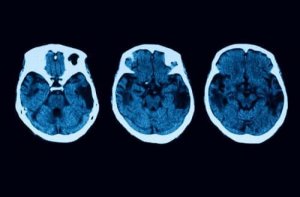

- 認知症の始まり:この病気である場合、神経画像検査で代謝の低下や血流の低下が見られます。しかし、認知症の症状は、この病気が非常に進行しているときに見られるものです。

しかし、診断検査はここで終わるわけではありません。疑いを払拭するために、MRIやコンピュータ断層撮影(CT)などの他の神経学的検査も行うことになるでしょう。すべての検査を通して後部皮質萎縮症であることが明らかになった場合、主に2つの治療法から選ぶことができます。